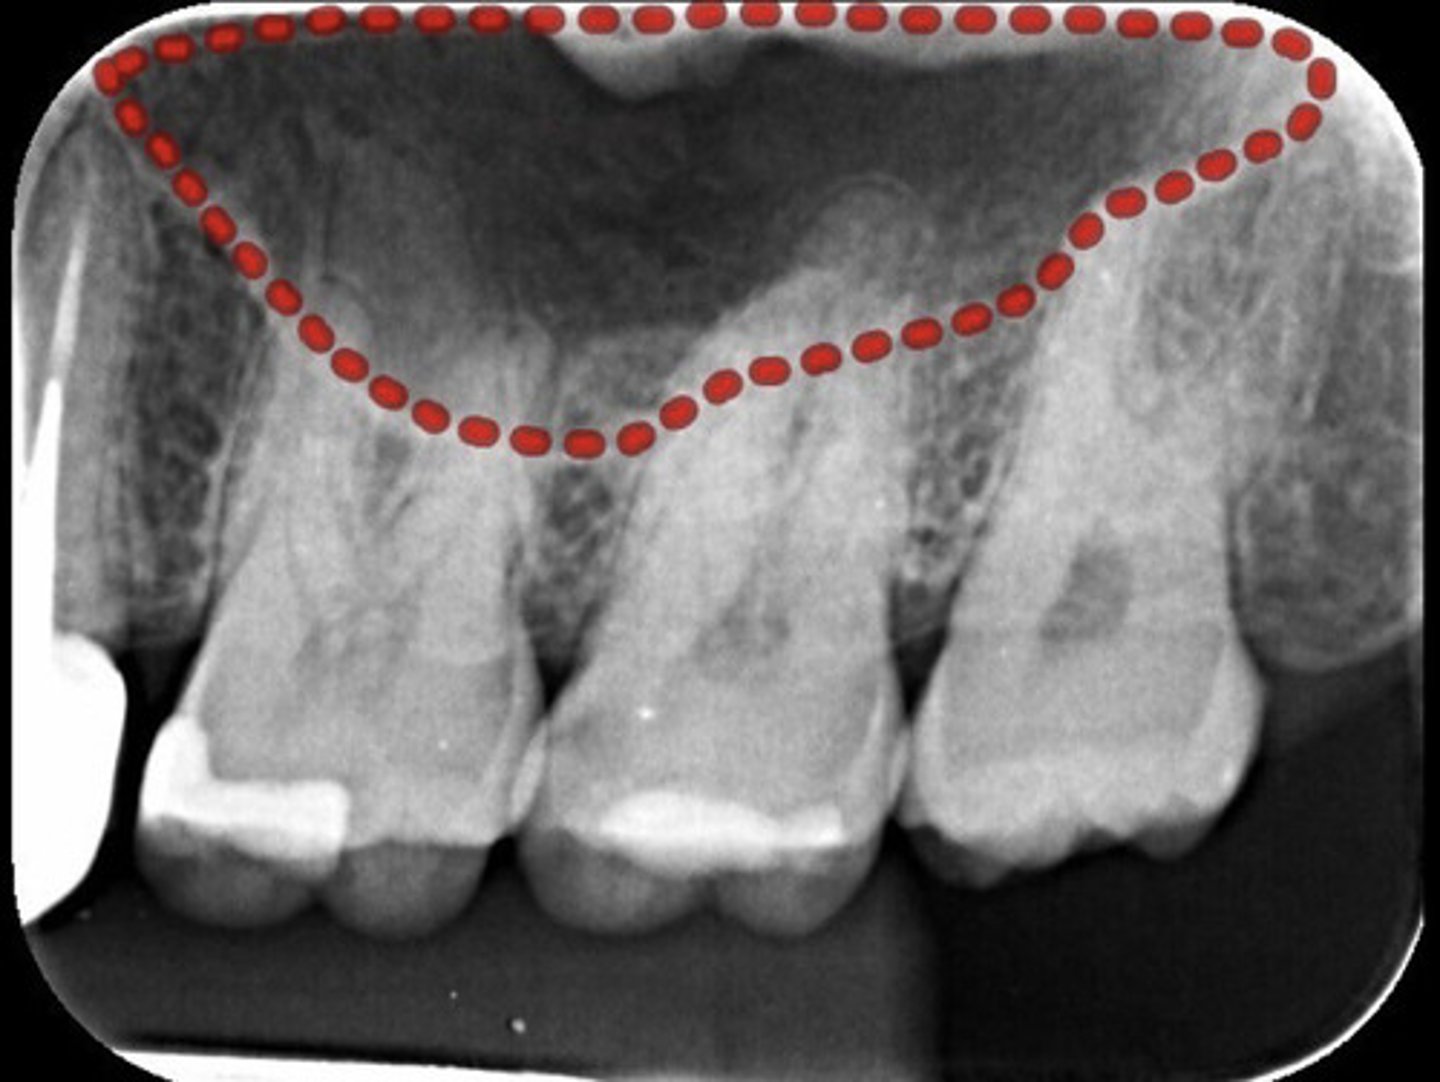

What are the red dots representing?

Dental papilla space